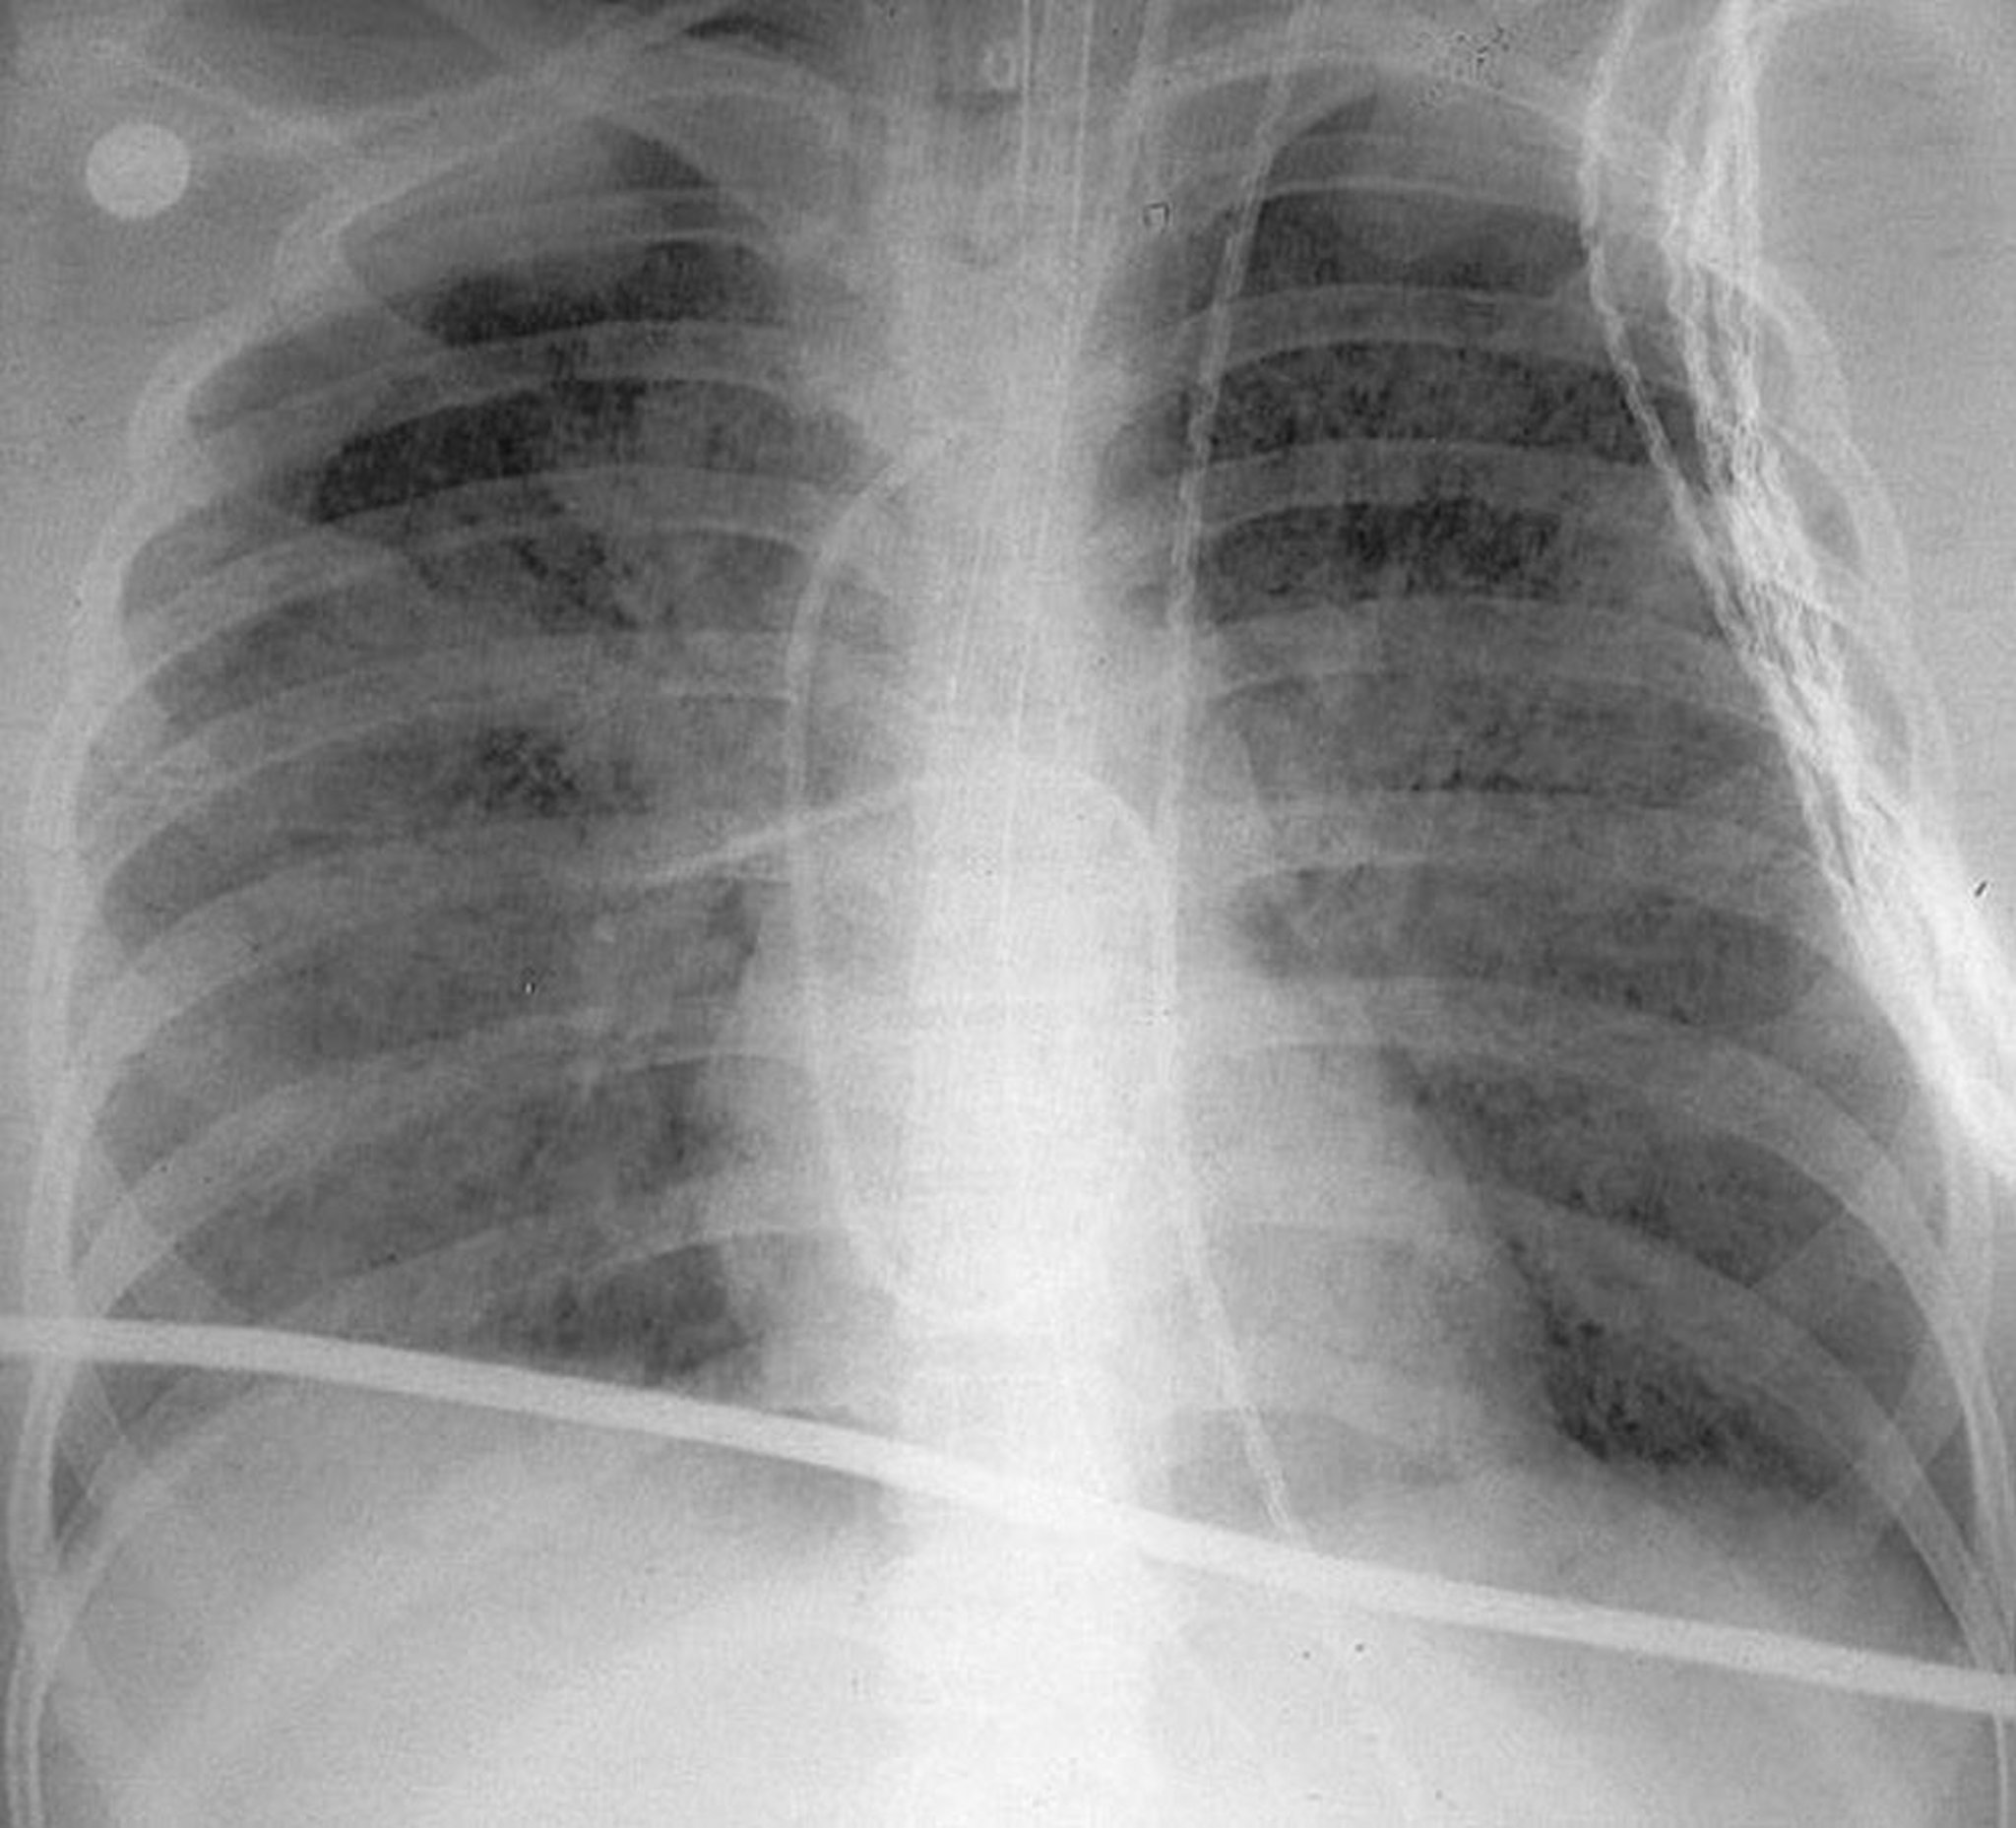

Cette radiographie thoracique verticale montre des opacités bilatérales diffuses caractéristiques du syndrome de détresse respiratoire aiguë (ARDS/SDRA [acute respiratory distress syndrome]).

By permission of the publisher. D'après Herdegen J, Bone R. In Atlas of Infectious Diseases: Pleuropulmonary and Bronchial Infections. Edited by G Mandell (series editor) and MS Simberkoff. Philadelphia, Current Medicine, 1996.